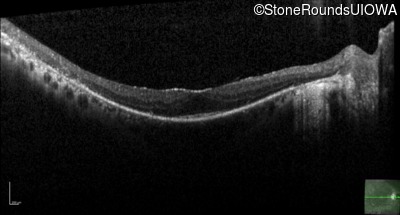

Optical Coherence Tomography - Right - 20/25 -2 sc

Exemplar / OCT Stack

OCT Stack